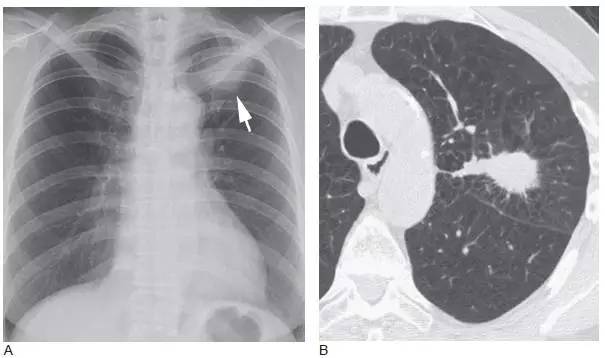

图5 局灶性细支气管肺泡癌(BAC)

A. 胸片显示了左肺边界很模糊的结节( 箭头);B.5mm 层厚的CT 显示了边界不清、不规则、毛刺状的结节,含空气支气管征和空泡征,为BAC 的典型征象

图6 局灶性细支气管肺泡癌

A.5mm 层厚的CT 显示边界不清的结节;B.HRCT 显示结节大部分呈磨玻璃样,为匍匐生长肿瘤的典型征象